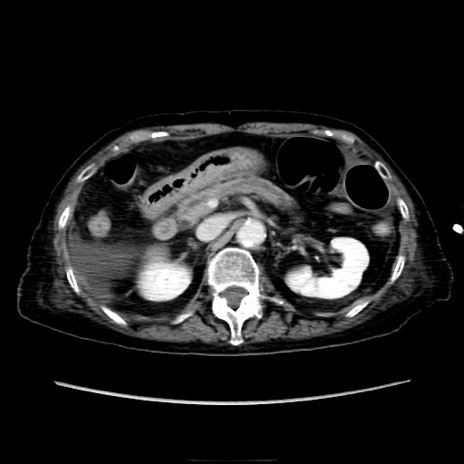

症例40(横断像)

【症例】90歳代女性

【主訴】腹痛・嘔吐

【現病歴】 食欲低下、嘔吐があり昨日他院受診。肺炎と診断され入院となる。入院後より腹部全体に圧痛あり。胃管留置され経過みていたが、症状持続するため、

当院転院となる。

【身体所見】腹部:中央に激痛あり、圧痛あり、反跳痛不明

【データ】WBC 17100、CRP 18.82